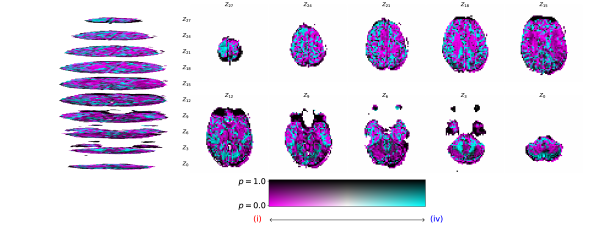

Figure 2 illustrates the distribution of residues (observed vs. estimated differences) on the fMRI volumes for the NODDI dataset. Clearly, by visual inspection, (iv) model has the darker and biggest area of shaded regions, which implies a better coverage across the brain regions and better synthesis quality. Models with topographical attention, (ii) and (iv), corresponding to Figures 2(b) and 2(d), respectively, significantly improve the synthesis, as shown by the darker and bigger areas against (i) and (iii) depicted in Figures 2(a) and 2(c), respectively. Particularly, we notice that models (i) and (iii) report difficulty in the retrieval of haemodynamical activity located in occipital and parietal lobes.

To better address which regions our baselines had more difficulty retrieving, the normalized residues were computed and are illustrated in Figure 3. Baselines – corresponding to models (i) and (ii), shown in Figures 3(a) and 3(b) respectively, which correspondingly implement a linear projection in the latent space and topographical attention –, have difficulty retrieving the prefrontal, occipital and parietal lobes, as the shade tends to a lighter grey in that region. Model (iv), shown in Figure 3(d), does not show a noticeable region with a lighter tone of grey, which implies no evident difficulty in retrieving haemodynamical activity across the different brain regions.